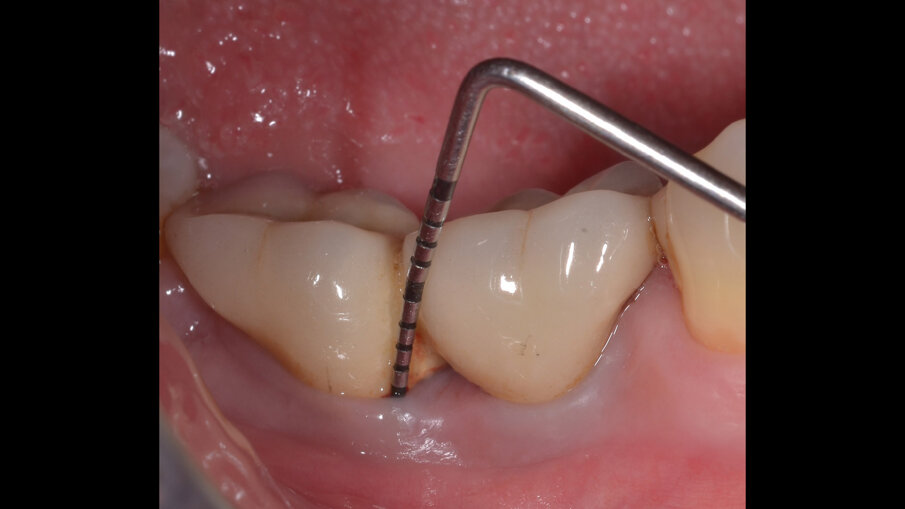

Il paziente, di sesso maschile e di 48 anni di età, è in buone condizioni di salute generale ma, a distanza di 10 anni dall’inserimento, presenta due impianti endossei, in posizione 4.6 e 4.7 con uniforme perdita ossea e con sondaggi di profondità variabile tra 6 e 9 mm accompagnati da sanguinamento, con tessuti marginali che mostrano importanti aspetti infiammatori, causa di sintomatologia dolorosa per il paziente (Figg. 1a-f).

I siti interessati sono stati strumentati per via non chirurgica, utilizzando strumenti manuali, strumenti ultrasonici e air polishing con eritritolo. Al termine della seduta è stato applicato il gel di ozono (Ozosan Gel - Bioactiva) all’interno delle tasche, lasciando agire il dispositivo per 8 minuti, quindi eseguendo lavaggio con soluzione fisiologica. Il post-operatorio ha avuto un decorso privo di dolore con rapida remissione della sintomatologia soggettiva. Il paziente è stato inserito in un programma di mantenimento parodontale trimestrale. A distanza di 6 mesi dal trattamento non chirurgico della perimplantite, i siti si presentano stabili con profondità di sondaggio ridotta tra i 3 e i 5 mm con assenza completa di sanguinamento al sondaggio (Figg. 1g-m).